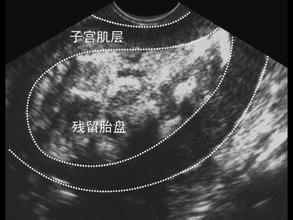

胎盘残留最大的危害性在于可导致子宫收缩不良,从而引起恶露淋漓不尽,甚至大出血的可能,另外亦可能导致宫内感染的发生,继而发展为盆腔炎。有多次孕产史或流产刮宫史的产妇,需高度重视胎盘残留的发生。分娩后需立即检查胎盘的完整性,确保无大块胎盘残留。出现产后出血增多或恶露淋漓不尽的患者,可行B超了解是否有少量胎盘碎片残留子宫内。

确诊胎盘残留很简单,通过简单的B超检查即可做到。而根据残留物的大小、恶露情况、胎盘残留的时间等,可选择保守治疗或手术治疗。一般情况下,残留物较小者可选择保守治疗,如缩宫素加强宫缩、生化汤、益母草等排瘀治疗。残留物较大、出血多或胎盘残留时间长的,及保守治疗无效的建议行清宫术为好。